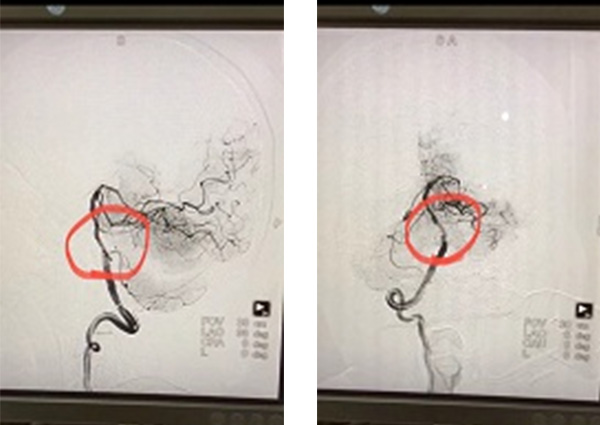

术前DSA

术后DSA

患者病情复杂,多次论证,制定严密手术方案,在患者病情稳定后的第二周,马明辉医生为患者进行了全麻下经皮基底动脉狭窄处血管成形术及支架置入术。实际上,手术的风险远比想象的大,马医生和他的同事们顶着巨大的压力,仅用时1.5个小时就成功将血管打通。术后患者苏醒,自诉症状得到了明显改善,复查头部CT:无出血转化;血常规、肾功能未见异常。术后第二天,解除压迫器后,患者就已经完全恢复正常了。家属连声致谢:“马医生医术真是太精湛了,我爸症状明显减轻了,而且住院这几天医生护士就像亲人一样照顾他,我为五院点赞。”

从死神手中夺生命,是马明辉医生日复一日的工作。急性脑血管病的治疗,关乎患者后续的生存质量,他不敢有丝毫怠慢,立即协助患者办理了住院,认真进行查体,结合CT结果,考虑患者可能存在严重血管病变,遂迅速完善相关血管因素检查和评估。DSA全脑血管造影提示:基底动脉起始段严重狭窄 ;左侧颈内动脉C5、C6轻度狭窄 ;左侧椎动脉显影不佳(非优势侧)—病根终于找到了。